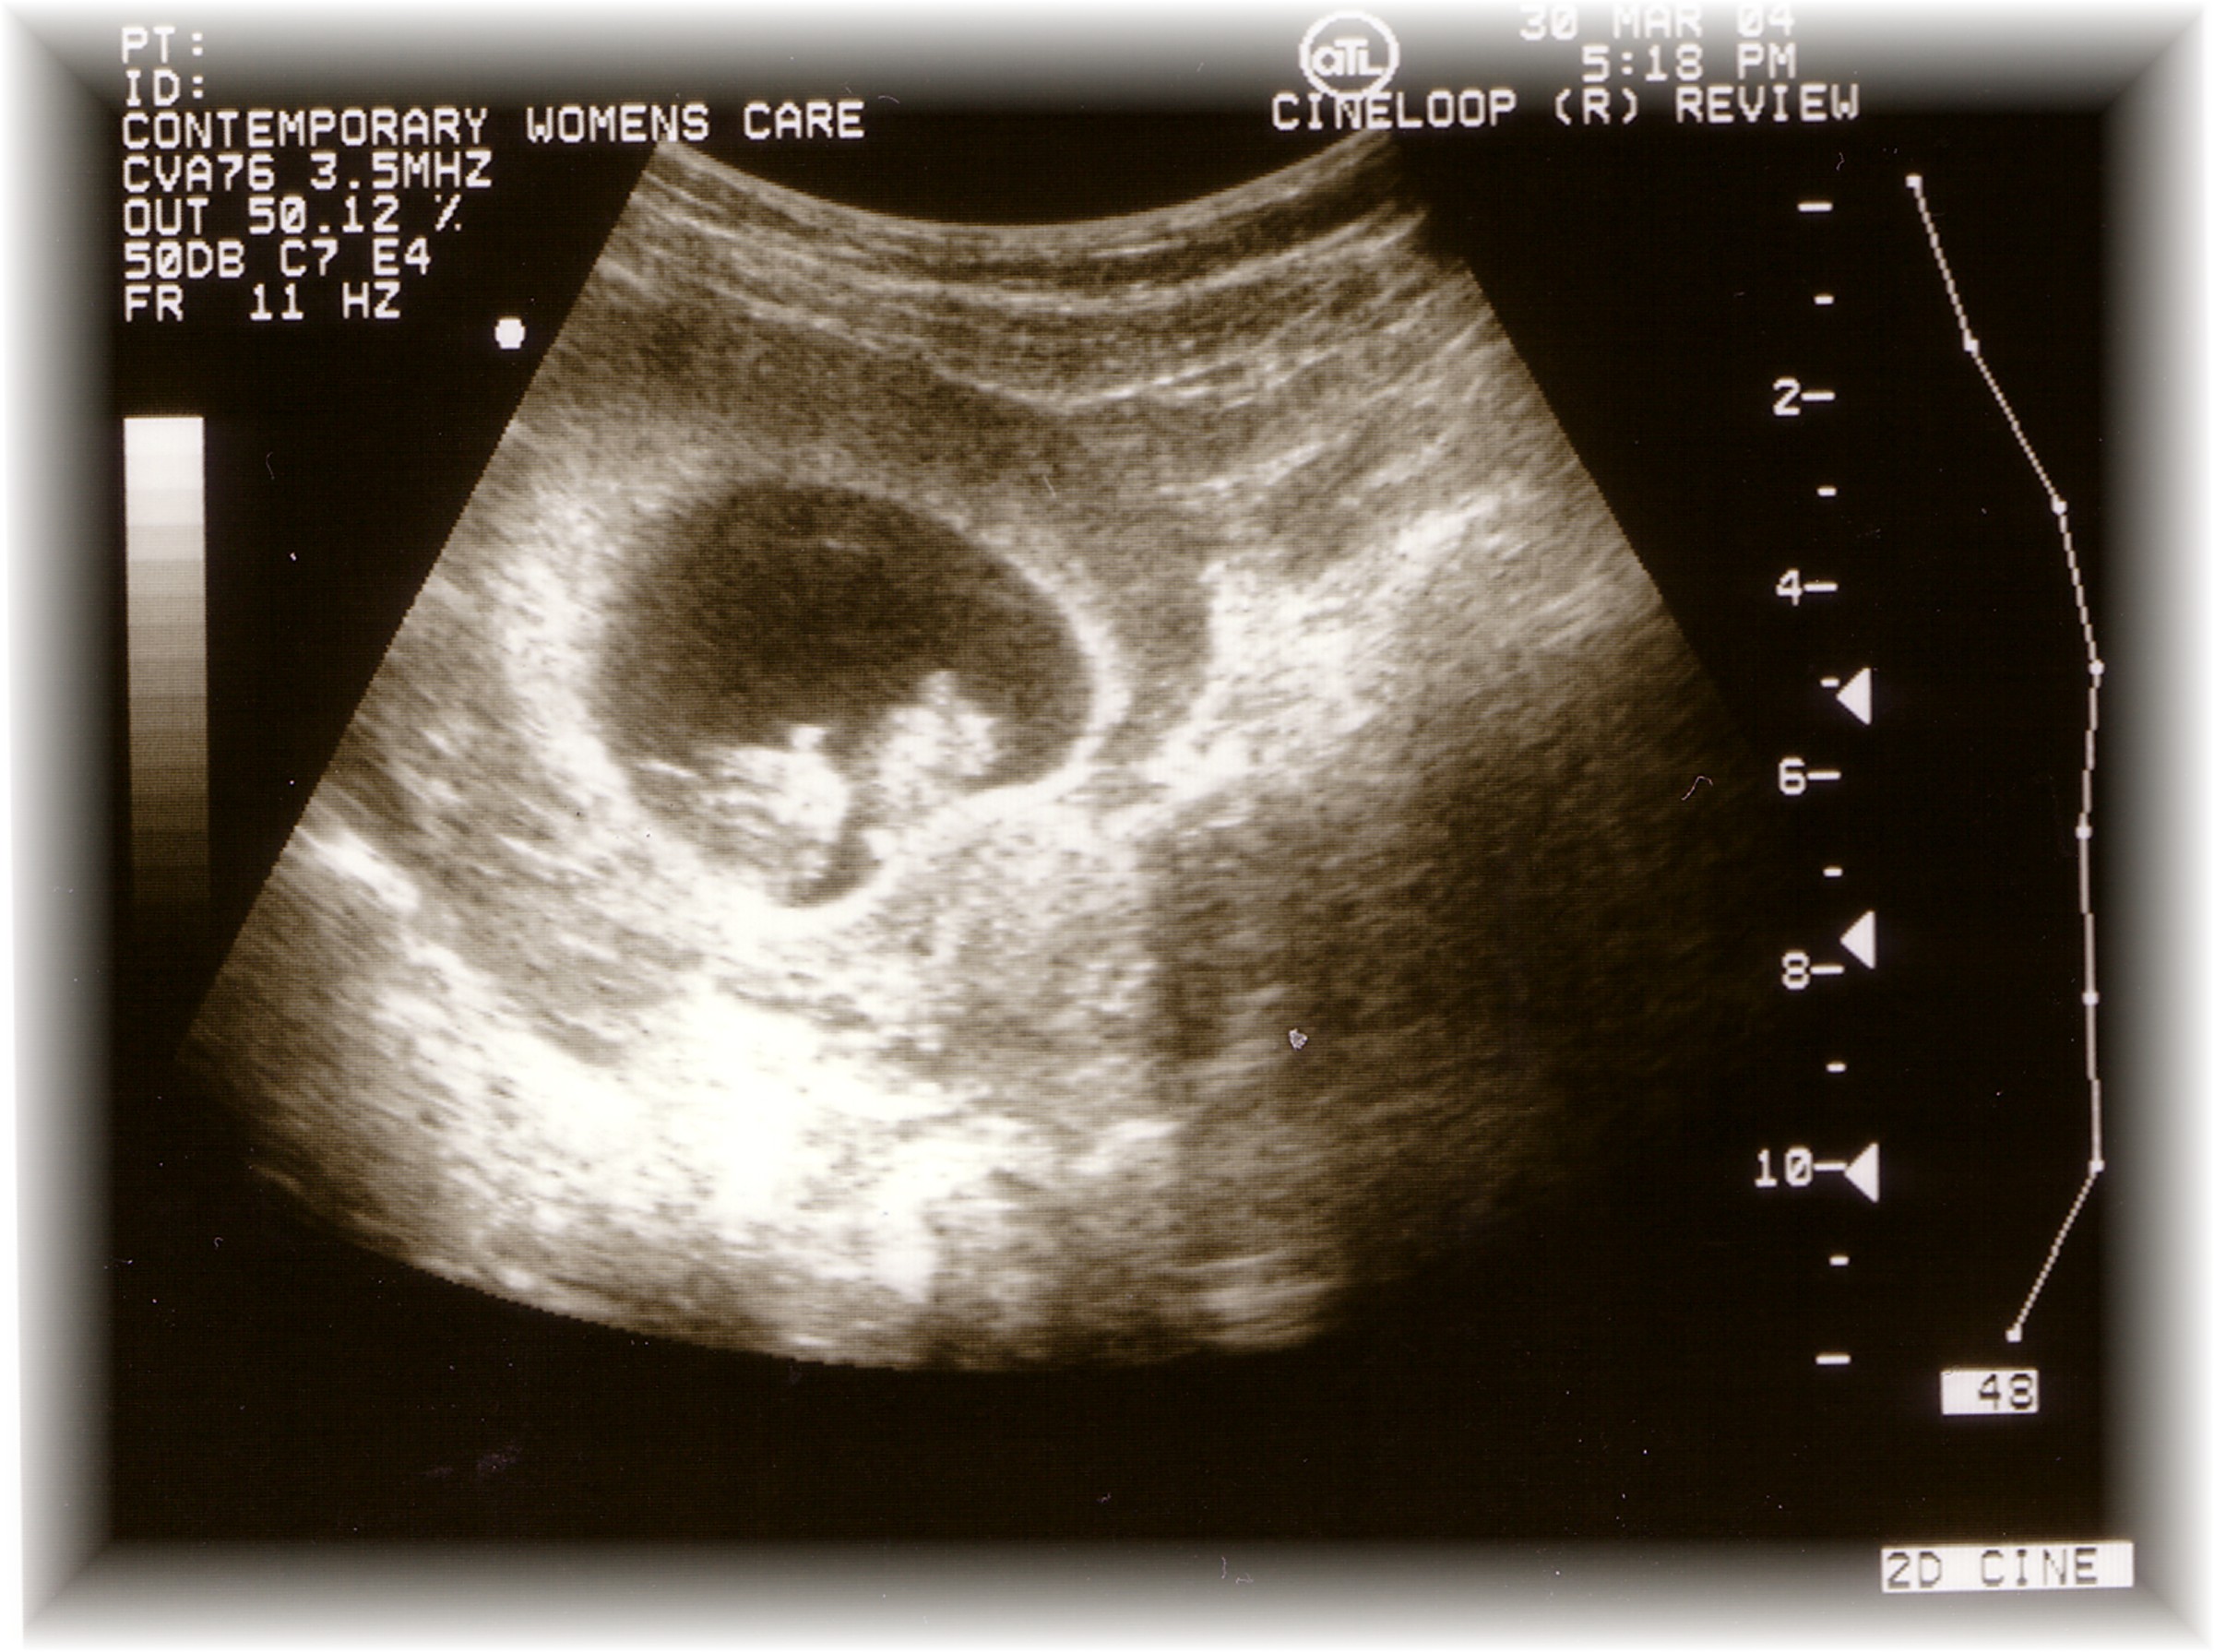

This is the famous "F You Pic!"